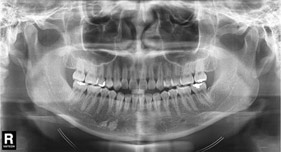

Radiografías: panorámica, pantomografía y ortopantomografía.